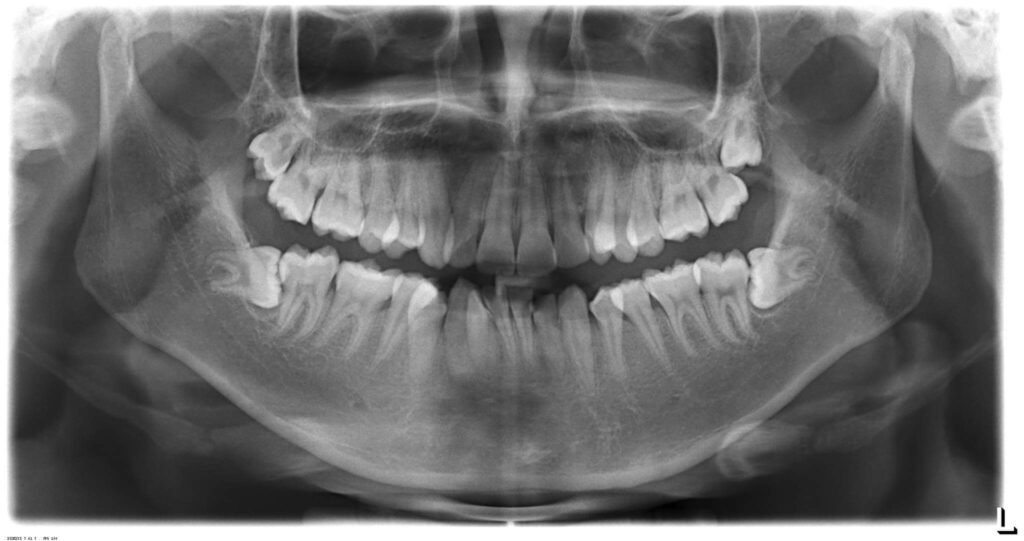

Bệnh nhân nam sinh năm 1998. Khớp cắn hạng I, với chen chúc và khấp khểnh nặng ở cả 2 hàm trên và dưới.

Cung hàm trên và cung hàm dưới đều hẹp, răng thiếu chỗ nghiệm trong.

Kế hoạch: Nhổ 4R4, chỉnh nha phân đoạn